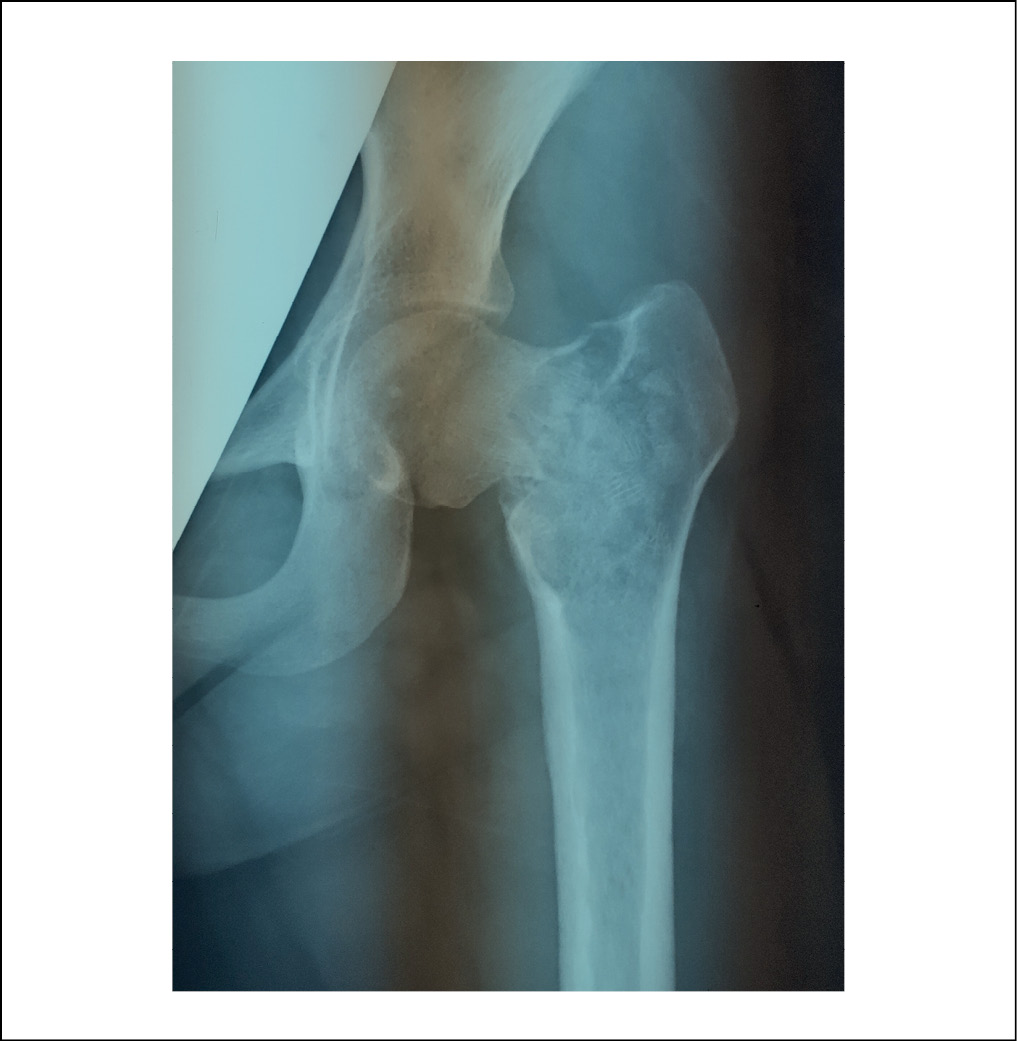

Пациентка K., 2000 г. p., в декабре 2017 года обратилась за консультацией в Клиники Самарского государственного медицинского университета по поводу случайно выявленного в ходе рентгенографии патологического образования проксимального отдела левой бедренной кости (рисунок 1).

Рисунок. 1. Рентгенограмма левого тазобедренного сустава пациентки К., 2000 г.р., в прямой проекции, 2017 г. Отмечаются признаки наличия солитарной костной кисты в проксимальном отделе бедренной кости (границы отмечены стрелками). / Figure 1. X-ray of the left hip joint of patient K., born in 2000, in direct projection, 2017. There are signs of a solitary bone cyst in the proximal femur (the borders are marked with arrows).